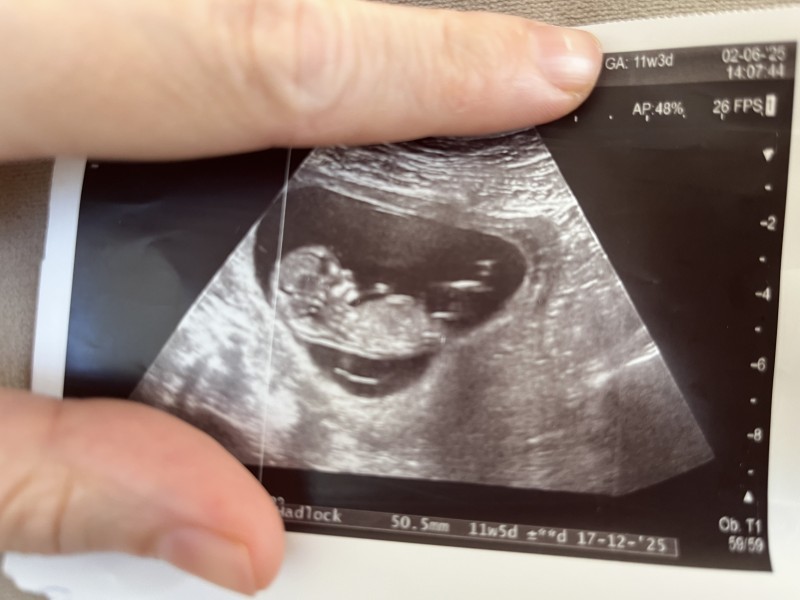

Cinsiyet tahmini yapar mısınızzz 😊 11+3

Erkek bence oğlumun ultrason resmine benziyor🌸 Rabbim sağ salim kavuştursun inşallah 🥰

Yok canım doktorum söylemedi benim ama 12 haftalıkken 2 li testte asistan kız AA bişey gördüm deyince anlamıştım az çok 🌸😁🌸17 haftalıkken %100 erkek deyip bacak arasıni göstermişti

Bende ikili teste gittiğimde emin değilim ama belki kız olabilir dedi hafta olarak küçük olduğu için kesin birsey diyemedi tabi bende bir buraya sorayım dedim 😊